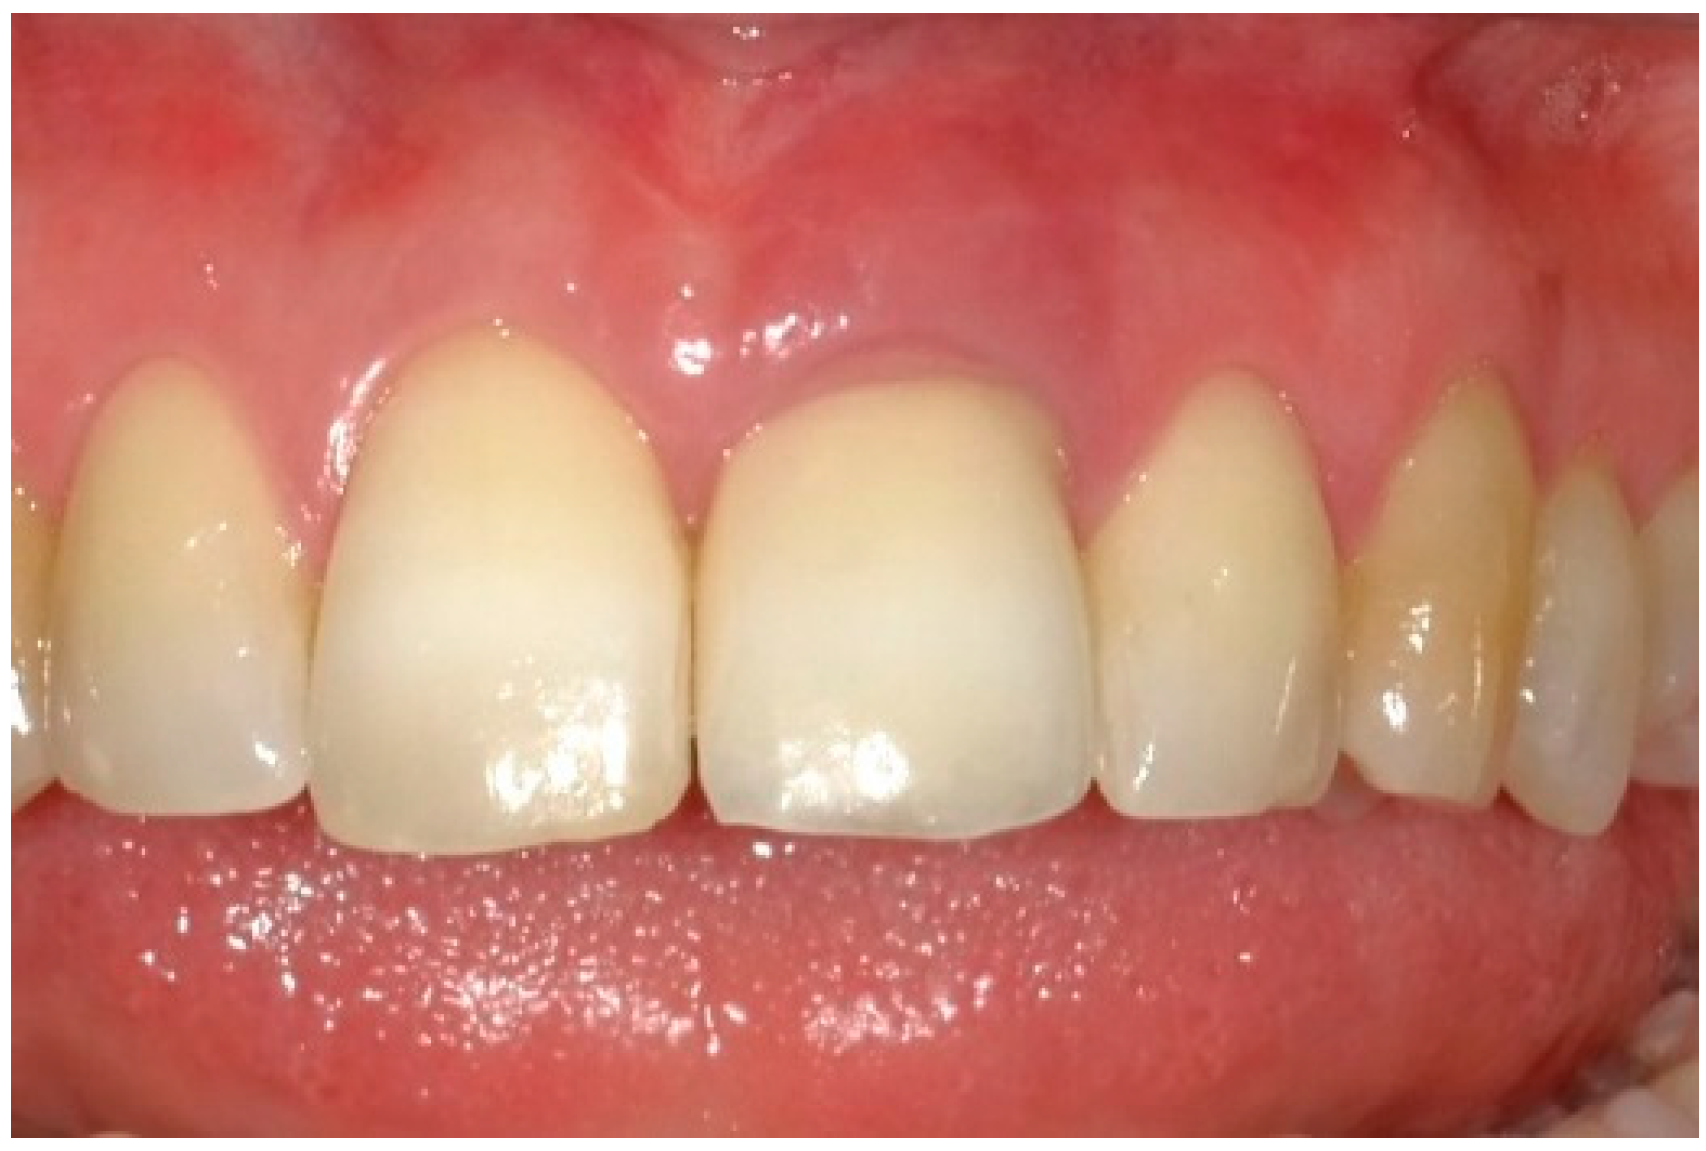

4. Timeline and Diagnostic Assessment

5. Therapeutic Intervention

5.1. Patient Diagnostics